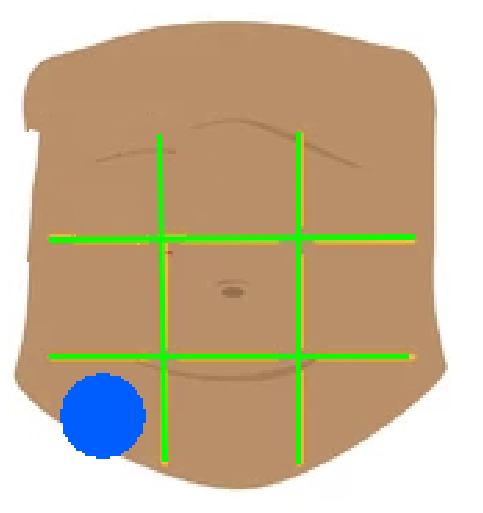

Right hypochondriac region

Left hypochondriac region

Epigastric region

Right lumbar region

Left lumbar region

Umbilical region

Right inguinal region

Left inguinal region

Hypogastric regions